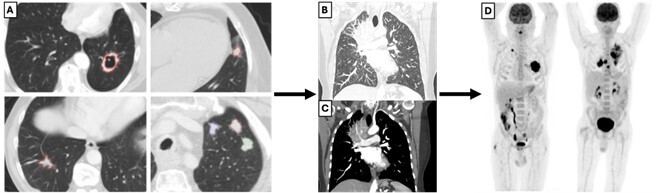

La sensibilité et la spécificité du taux de PSA ne sont pas absolues. Dans certains cas, l’IRM peut être utilisée pour évaluer la prostate et localiser les lésions suspectes. Elle est interprétée en utilisant les critères Prostate Imaging- Reporting and Data System (PI-RADS). PI-RADS est un ensemble de directives pour l’interprétation de l’IRM de la prostate améliorant la détection du cancer cliniquement significatif. La version 2 de PI-RADS met l’accent sur l’utilisation du coefficient d’atténuation de diffusion  (ADC) et de l’IRM pondérée en diffusion pour les anomalies de la zone périphérique, et sur l’IRM pondérée en T2 pour la zone de transition, simplifiant l’évaluation des images contrastées. En cas de forte suspicion de cancer de la prostate avec IRM et biopsies négatives, la TEP-TDM au PSMA (antigène membranaire spécifique de la prostate) permet la détection d’un cancer de la prostate cliniquement significatif chez environ la moitié des patients. Dans cette situation, la TEP-TDM au PSMA peut guider la biopsie de deuxième intention (fig. 1).

Lorsqu’un cancer de la prostate à haut risque (ou intermédiaire défavorable) selon la classification pronostique d’Amico est diagnostiqué, un bilan d’extension par examens d’imagerie complémentaires est réalisé. Ces examens visent à détecter les métastases lymphatiques et osseuses. Bien que l’imagerie conventionnelle (TDM thoraco-abdomino-pelvienne et tomo­scintigraphie osseuse) reste un standard, depuis 2021, la TEP-TDM au PSMA se généralise dans cette indication, avec une meilleure précision diagnostique sur l’atteinte ganglionnaire pelvienne et métastatique à distance et une accessibilité croissante sur le territoire français.5

Les performances de la TEP-TDM au PSMA sont ­supérieures à celles de l’imagerie conventionnelle (scanner et tomoscintigraphie osseuse) lors du bilan d’extension initial (lorsque celui-ci est indiqué) et dans le bilan d’extension des récidives biologiques (fig. 1).4 Elle peut également être utile, en deuxième intention, pour cibler les biopsies prostatiques.